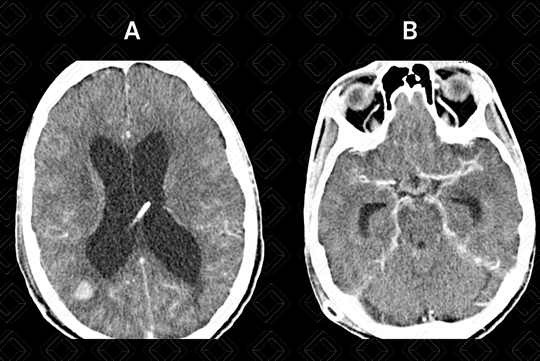

Texto alternativo para a imagem Figura 3. Créditos: Dra Elazir Mota - Rio de Janeiro/RJ

Descrição da lesão (figura 3): Tomografia computadorizada de crânio com contraste venoso. A: Lesão arredondada com captação anelar pelo meio de contraste na região parietal direita (tuberculoma). B: Intenso realce pós contraste nas cisternas da base, por meningite tuberculosa.